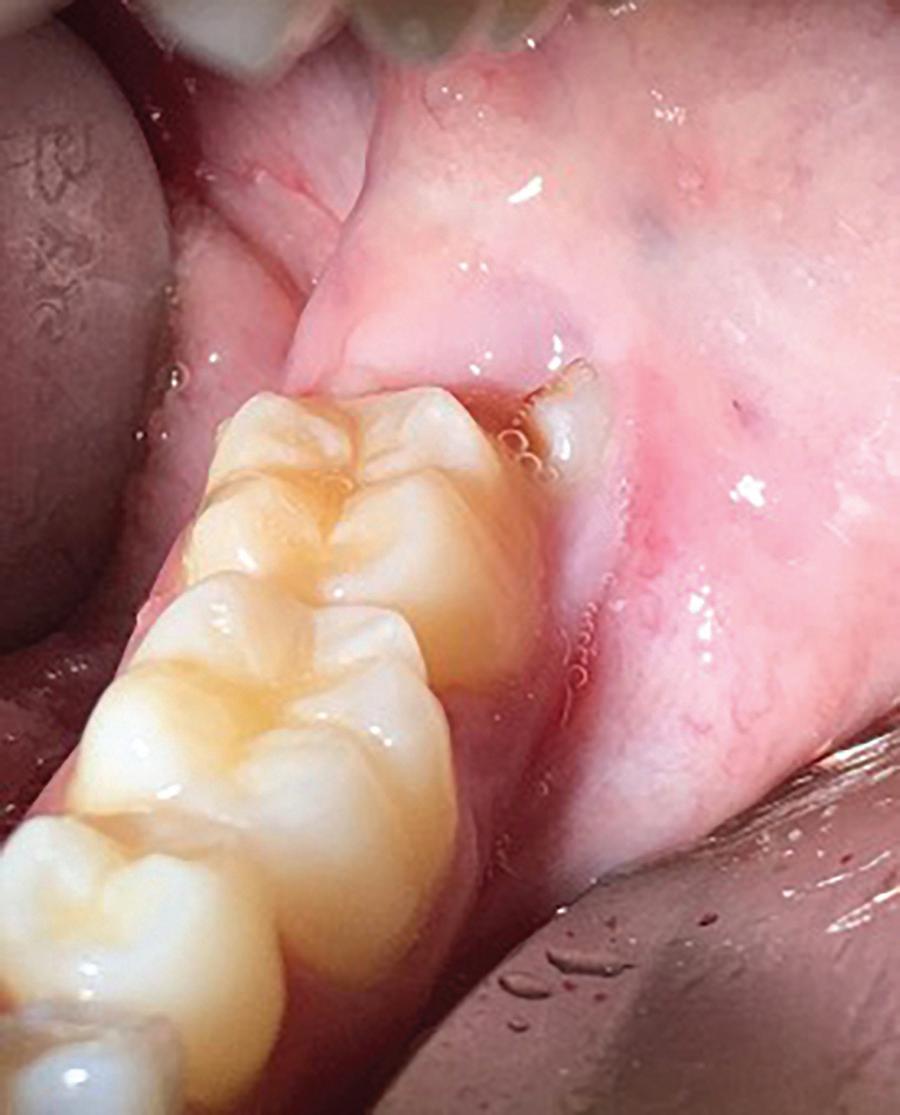

59 Oral Medicine, Oral Diagnosis, Oral Pathology

Malignant transformation of oral lichen planus after 6 years: a case report